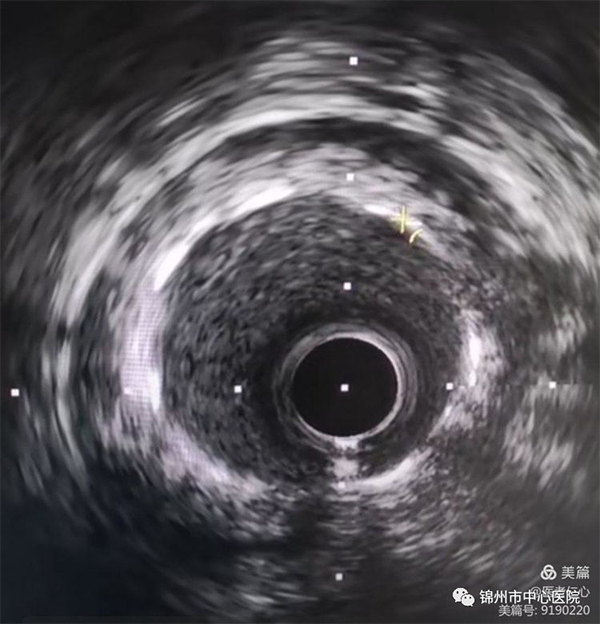

隨著心臟血管病變復(fù)雜性增加,錦州市中心醫(yī)院冠脈介入治療技術(shù)方法不斷更新,近日,借助血管內(nèi)超聲檢查,指導(dǎo)兩位冠心病患者冠脈介入治療方案,手術(shù)取得滿意效果。

冠狀動(dòng)脈造影一直被認(rèn)為是診斷冠心病的“金標(biāo)準(zhǔn)”。但在臨床中某些冠狀動(dòng)脈造影顯示管腔情況“正?!钡难軆?nèi)可出現(xiàn)各種粥樣斑塊病變,并有明顯的管腔狹窄。為了提升診斷治療水平,醫(yī)院引進(jìn)血管內(nèi)超聲,并廣泛應(yīng)用于臨床,取得了精準(zhǔn)治療的良好效果。

血管內(nèi)超聲(IVUS) 是無創(chuàng)性超聲技術(shù)和有創(chuàng)性的導(dǎo)管技術(shù)相結(jié)合,使用末端連接有超聲探針的特殊導(dǎo)管進(jìn)行的醫(yī)學(xué)成像技術(shù)。不僅可準(zhǔn)確測量管腔及粥樣斑塊或纖維斑塊的大小,更重要的是它可提供粥樣斑塊的大體組織信息,幫助醫(yī)生準(zhǔn)確評估冠脈狹窄的程度。被形象的稱為冠脈精準(zhǔn)介入治療的“第三只眼睛”。

冠脈造影與血管內(nèi)超聲相輔相成,可以有效指導(dǎo)治療方案,提高冠脈介入的質(zhì)量。